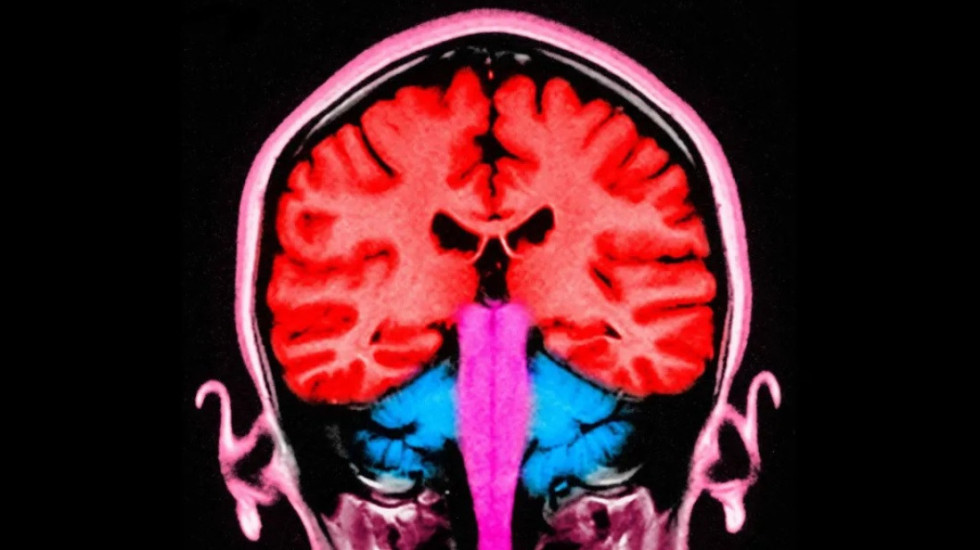

Gjatë eksperimentit, një rrymë elektrike u aplikua në zonat frontale dhe parietale të trurit, të vendosura në pjesën e përparme dhe në pjesën e pasme. Kur këto zona u stimuluan në të njëjtën kohë, pjesëmarrësit dhanë më shumë para.

Studiuesit përcaktuan dy zonat e trurit që dukeshin se "flisnin me njëra-tjetrën" - me qelizat e trurit që godisnin në të njëjtën frekuencë, kur lojtarët jepnin më shumë para.

Ato dy zona të trurit dihet se luajnë një rol në vendimmarrje dhe në empati, ose në dallimin e ndjenjave të të tjerëve nga tonat.